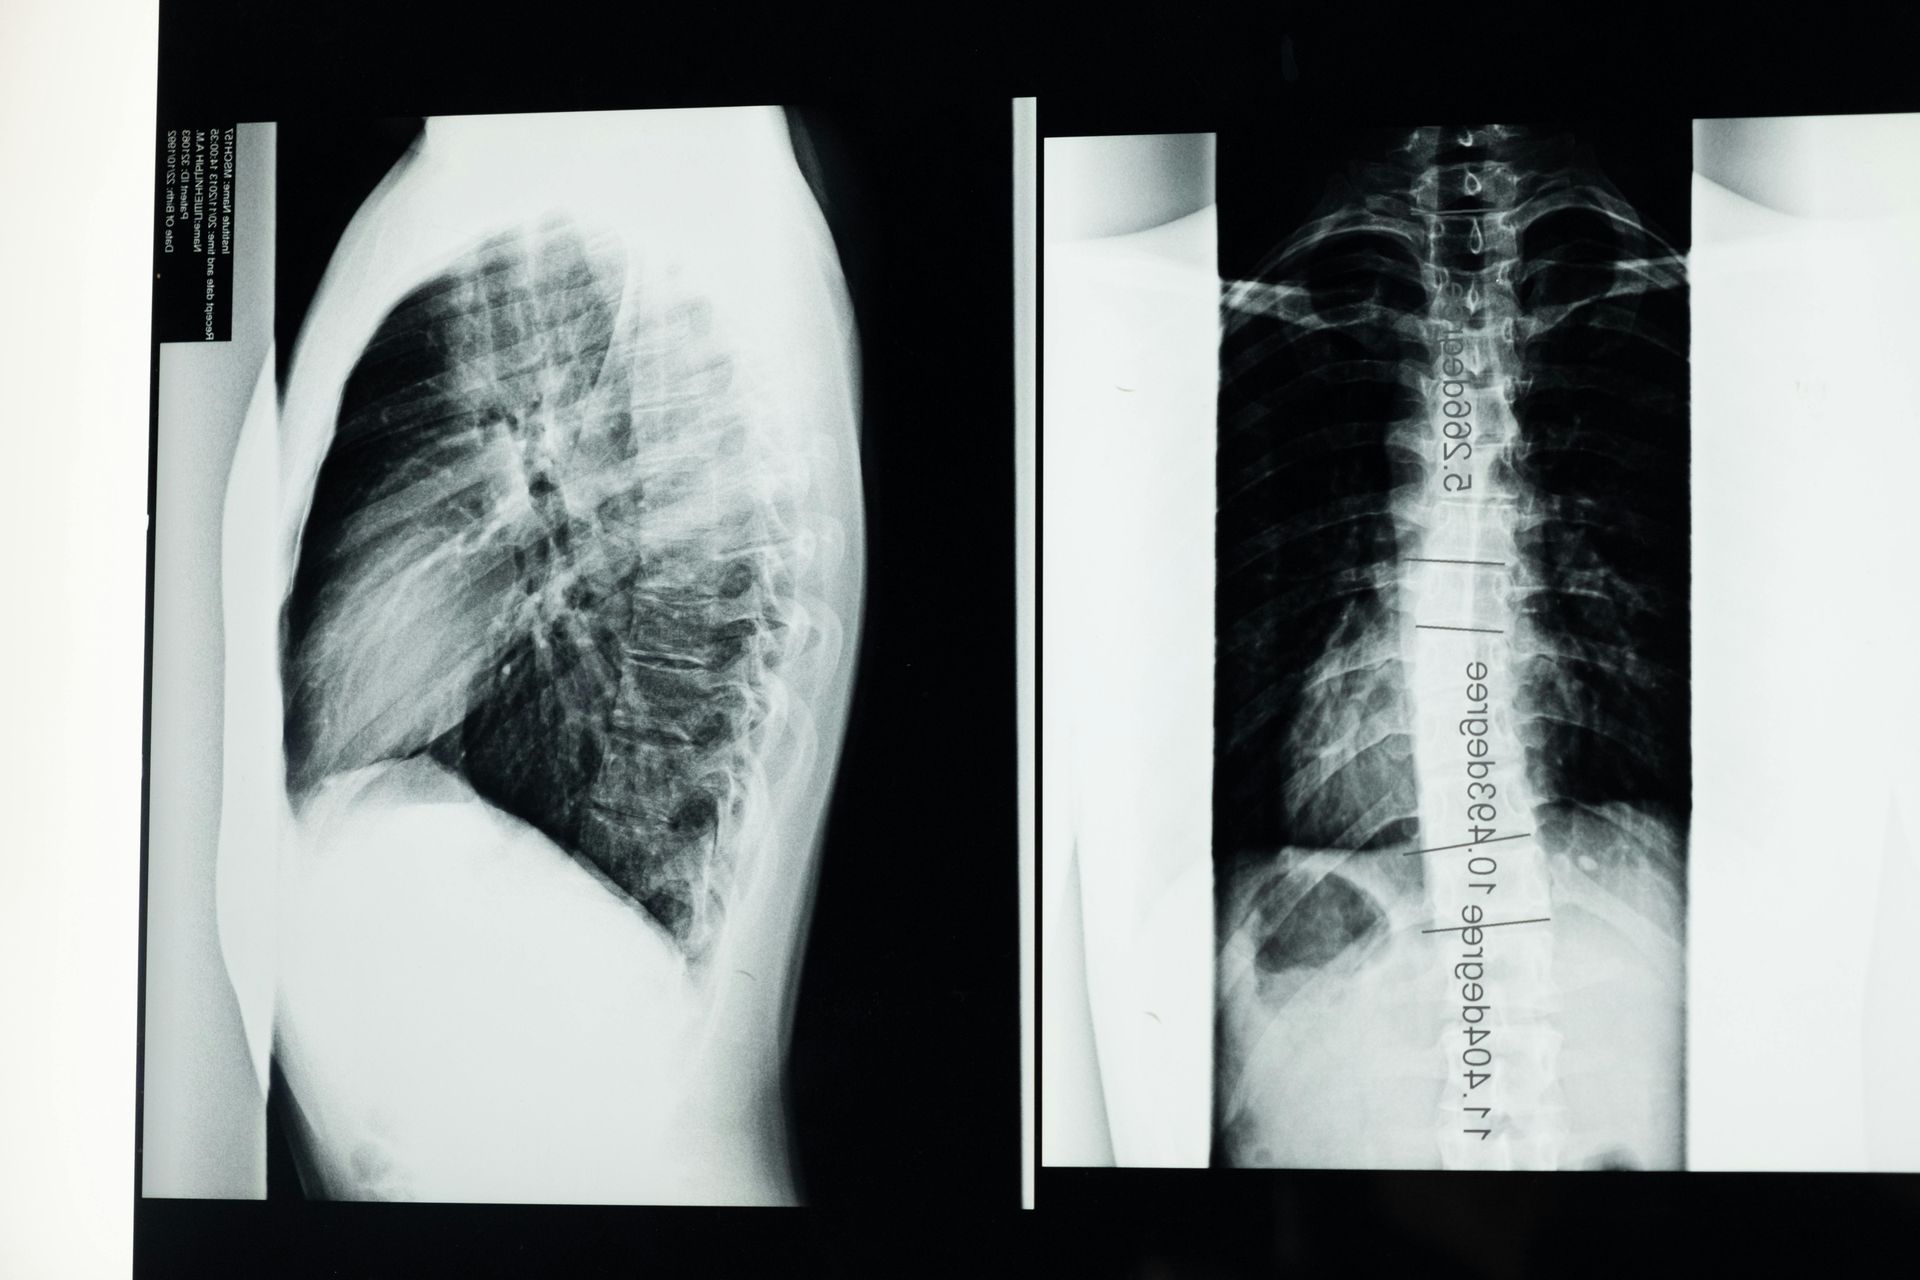

Your first visit includes a detailed assessment following your scoliosis diagnosis with a certified Schroth therapist. They'll review your x-rays, examine your spine, and create a customized exercise program for your specific curve.